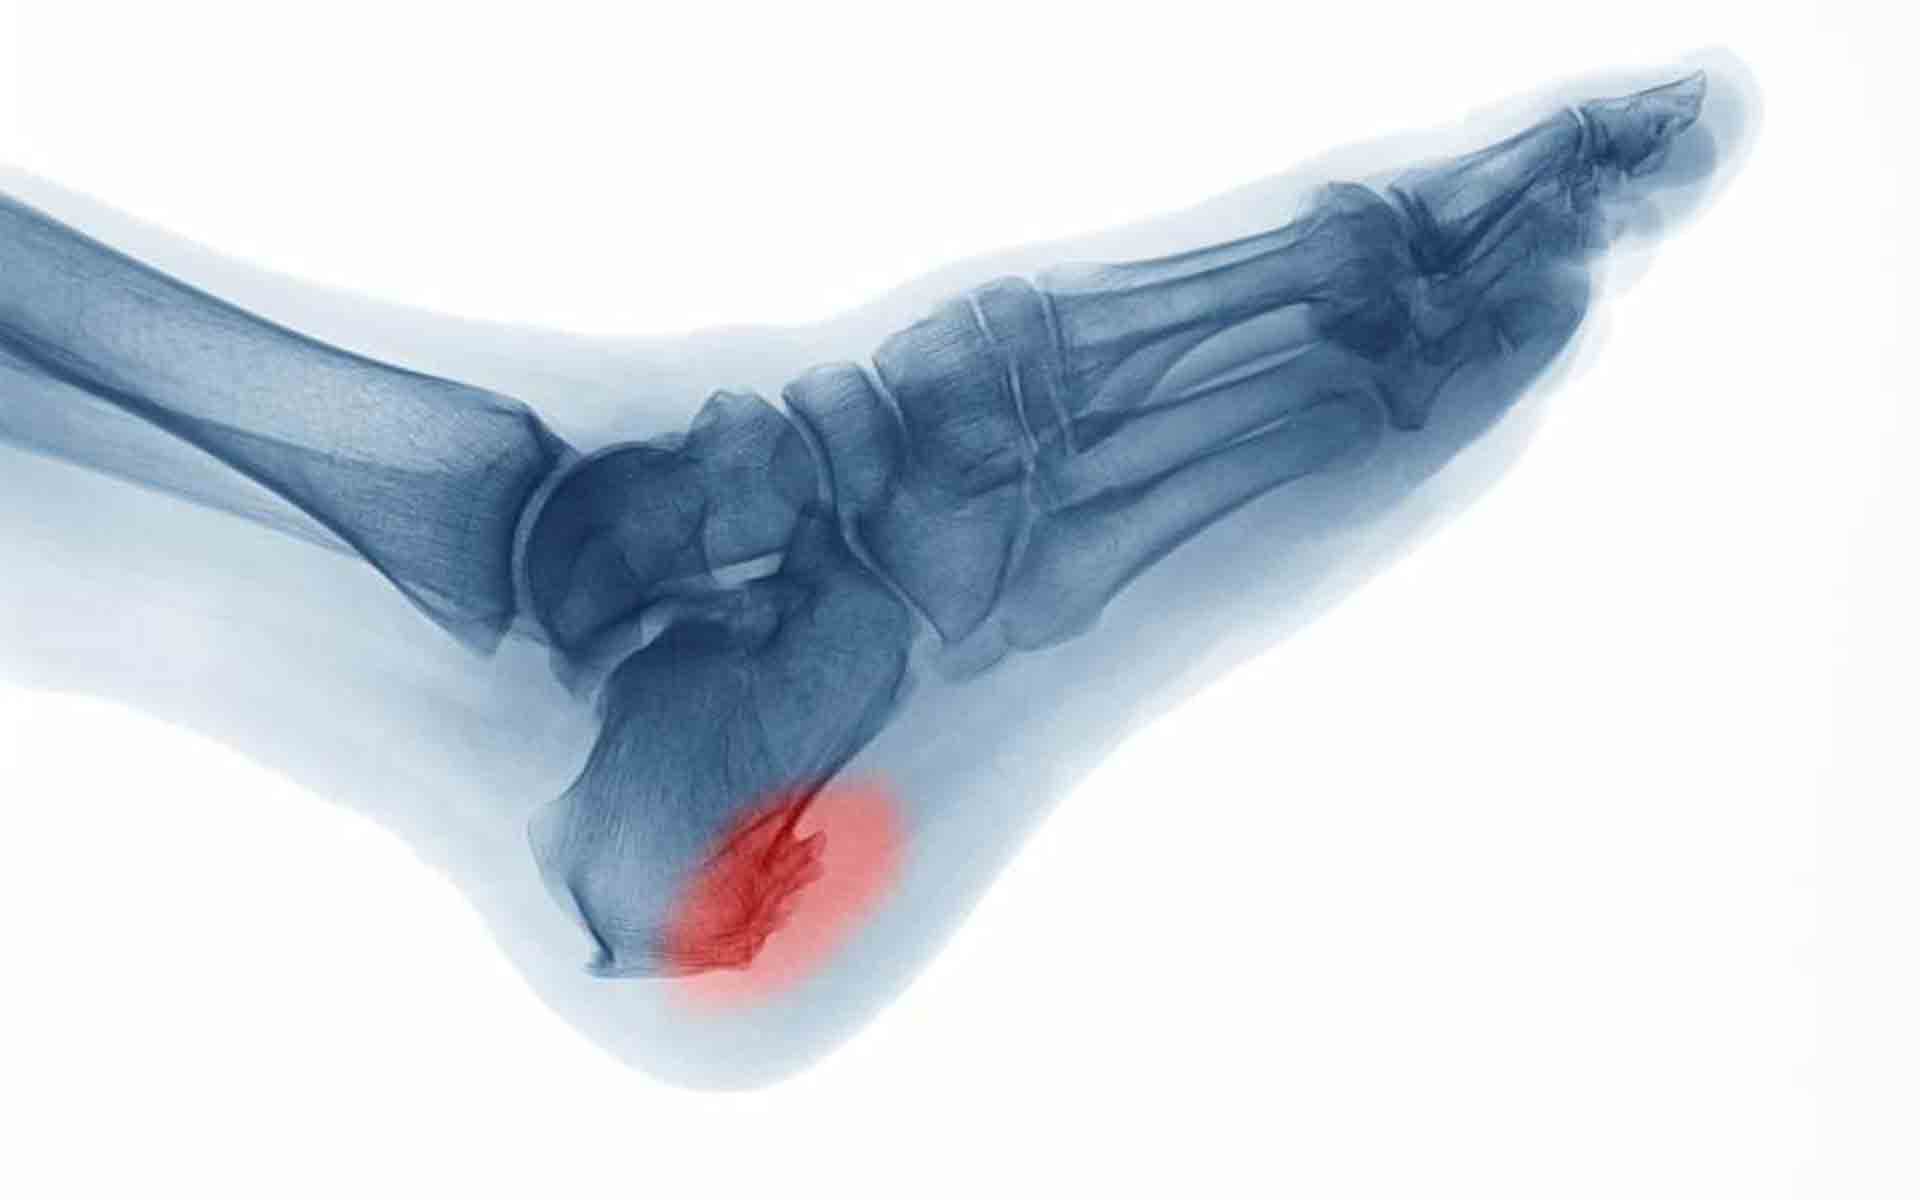

Espolones calcáneos

Los espolones calcáneos son una de las consecuencias más comunes de no tratar adecuadamente la fascitis plantar. En un intento de proteger el arco plantar y mitigar el daño, el cuerpo envía células donde se encuentra el problema para intentar solucionarlos. Estas células depositan calcio en el área. Con el tiempo, estos depósitos pueden crear unas protrusiones puntiagudas que se incrustan en la almohadilla grasas del talón, causando un gran dolor con cada paso que das.

Los espolones calcáneos se originan durante varios meses sin causar dolor. En otras palabra, permitir que la fascitis plantar siga sin tratar puede significar que se vayan gestando otros problemas secundarios sin que te des cuenta, hasta que aparece el dolor.